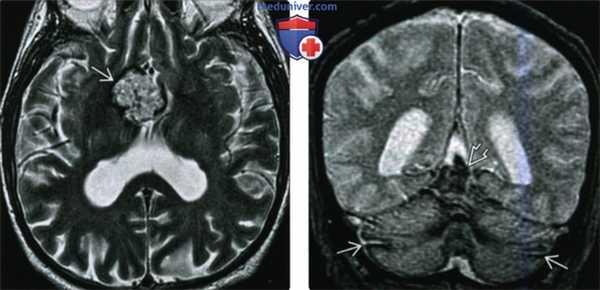

(а) MPT, Т2* GRE, аксиальный срез: у мужчины 57 года с двусторонней нейросенсорной тугоухостью и наличием в анамнезе давней резекции олигодендроглиомы лобной доли на поверхности ствола мозга, ЧН IX-XI, в области листков мозжечка , а также сосудистого сплетения IV желудочка определяются гипоинтенсивные наслоения.

(б) Более краниальный аксиальный срез: у того же пациента определяется поверхностный сидероз (ПС) VII и VIII ЧН, а также в области эпендимы IV желудочка.

(а) MPT, Т2* GRE, более краниальный аксиальный срез: у этого же пациента определяется диффузный ПС, локализующийся вдоль обеих сильвиевых борозд, а также в области поверхности среднего мозга, вершины червя мозжечка.

(б) MPT, Т2* GRE, более краниальный аксиальный срез: вдоль поверхностей обеих сильвиевых борозд, а также межполушарной борозды определяются наслоения. Обратите внимание на гемосидериновое окрашивание эпендимы, сосудистых сплетений боковых желудочков. (а) МРТ, Т2-ВИ, аксиальный срез: у мужчины 60 лет с прогрессирующей атаксией, двусторонней нейросенсорной тугоухостью определяется ПС, визуализируемый как «утолщение» и «черное очертание» обоих ЧН VIII. Обратите внимание на мозжечковую атрофию, увеличение размеров IV желудочка, усиление фолиации мозжечка.

(б) Иногда ПС ограничивается локализацией в задней черепной ямке. MPT, Т2* GRE, корональный срез: определяется обширный поверхностный сидероз структур задней черепной ямки. Участки «выцветания» изображения в области поверхностей мозговых структур, обусловленные отложением гемосидерина, визуализируются как гипоинтенсивные их очертания. Также ПС затрагивает верхний отдел червя мозжечка и его листки.